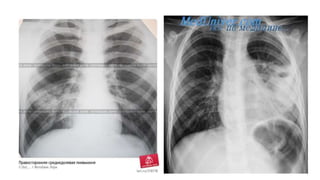

Клініка

Сегментарна

пневмонія

Рентгенографія легень

• рентгенологічна картина залежить від фази розвитку

запального процесу. В період вираженої клінічної

картини виявляють вогнищеві тіні різних розмірів ,

частіше розміщених локалізовано.

• При сегментарних пневмоніях – гомогенна тінь з чіткими

контурами в межах сегменту